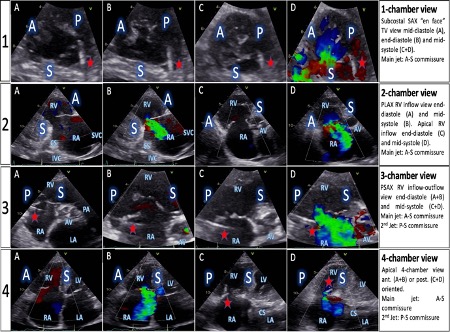

Background: Transcatheter tricuspid valve repair (TTVR) is an emerging option for treating high-grade tricuspid regurgitation (TR), mostly performed by edge-to-edge repair, and always guided by transesophageal echocardiography (TOE). In patients with excellent acoustic window, transthoracic echocardiography (TTE) can also provide a comprehensive understanding of tricuspid valve (TV) morphology. Also, in TTVR there is no need for transseptal puncture. Purpose: We sought to determine if edge-to-edge TTVR can be successfully conducted by a novel TTE guiding approach, in conjunction with fluoroscopy. Methods: 30 consecutive patients, scheduled for TTVR, were assigned to a TTE group (n=10), in the presence of excellent acoustic window, and a TOE group (n=20). On top of fluoroscopy, TTVR was guided exclusively by TTE in the first group, with TOE result confirmation solely upon clip release, due to safety reasons. The second group underwent classical TOE guidance. Understanding the 4 right heart chamber views (Fig. 1) and their respective fluoroscopic angulations (Fig.2) was paramount. TR severity, parameters of quality of life and functional capacity were assessed and compared between-groups, at baseline and up to 12 months. Results: Except for lower BMI (TTE 22.3±0.8 vs TOE 29.8±4.3, p<0.001), other baseline characteristics were very similar between groups, e.g., age (81.7±3.9 vs 82.8±4.1, p=0.483) or EuroSCORE II (11.9±10.3 vs 10.4±8, p=0.692). Device success was achieved in all patients, with a total of 15 implanted clips in the TTE group (mean no. of clips / patient 1.5±0.7) and 31 clips in the TOE group (1.5±0.6). Device time (75±37.1 vs 65.7±31.3 minutes, p=0.506) and fluoroscopy duration (16.3±10.5 vs 14.4±7.2 minutes, p=0.564) were also close. TR reduction was successful in all but one patient, in each group (90% vs 95%, p=1.000). TR improvement was equal between-groups, with 2- or more grade reduction in 60% of each group, at 30 days. Thus, grade IV/V and V/V TR, present in 60% of all patients at baseline, dropped to 10% (1/10 vs 2/20, p=1.000) by procedure end and follow-up. No device associated complications occurred. After 12 months, mortality was 13.3%, with one non-cardiac death. At one-year follow-up, all remaining patients had at least one grade reduction in NYHA class (9/9 vs 17/17, p=1.000). Kansas City Cardiomyopathy Questionnaire score and 6-minute walk distance similarly improved (∆24.8±21.4 vs 20.1±13.6 points, p=0.227; ∆93.5±100.4 vs 80.8±64 meters, p=0.121). An in-group difference was also noticed in renal function improvement by follow-up [glomerular filtration rate (GFR) TTE group: 56.8±18.7 to 64.6±14.9 ml/m2/1,73m2, p=0.050; TOE group: 50.7±19.9 vs 53.8±20.9, p=0.347]. Conclusion: TTE guidance of TTVR is feasible and safe, provided very good acoustic window. Furthermore, it can offer the same amount of information and be as valuable as TOE. The data encourages screening for a possible TTE guidance approach, even if performed in part with TOE assistance. Such combined imaging guidance could soon make general anesthesia obsolete, which is the main procedural inconvenient in already very sick TTVR patients. The concept of the 4 right-sided chamber views, seen from TTE, TOE, fluoroscopy and CT perspectives, creates a common language between TTVR team members. Successful TR reduction, irrespective of guidance method, led to significant improvement in quality of life after one year. |